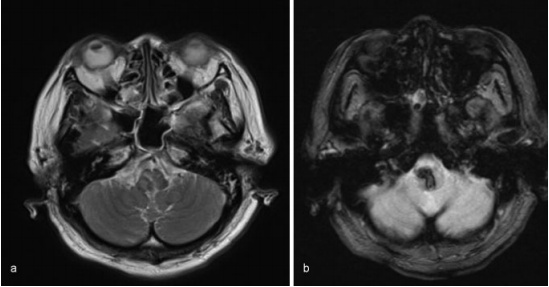

入院后,她出现白天呼吸抑制(每分钟呼吸10次)和夜间呼吸暂停。然后她被插管,并用呼吸机控制呼吸。MRI未发现明显的出血原因,如海绵状畸形、动静脉畸形或肿瘤。患者随后被诊断为高血压原发性延髓出血,随后通过持续静脉注射钙通道阻滞剂来降低血压。然而,病人的呼吸抑制没有改善。

图:磁共振图像显示出血没有明显的病理原因,(a)T2加权(b)T2加权。